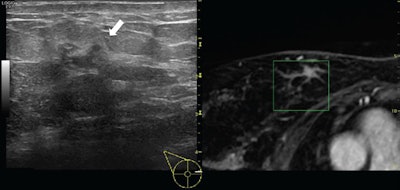

Ultrasound image (left) with the corresponding multiplanar reconstructed MR image (right) of a 54-year-old woman with a suspicious lesion at the upper-internal quadrant of the right breast. MR imaging showed an irregular branched enhancing lesion of 23 mm, undetected at second-look ultrasound. Second-look ultrasound with volume navigation showed the corresponding area (white arrow). Pathology obtained with ultrasound-guided biopsy with volume navigation demonstrated an invasive ductal carcinoma with an extensive intraductal component (green box). All images courtesy of Dr. Alfonso Fausto.In the current study, they present the results of a six-year assessment of second-look ultrasound of additional breast lesions with volume navigation using supine contrast-enhanced MRI coregistered during live ultrasound exams to analyze its clinical value using pathology as a reference, and to assess the need for MRI-guided biopsies.